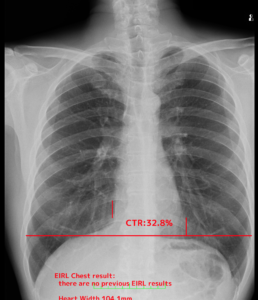

その他心胸比という心臓の大きさを自動で計測してくれて、心不全の管理に役立ちます。

結節影はありませんでした。心胸比32.8%とでています。